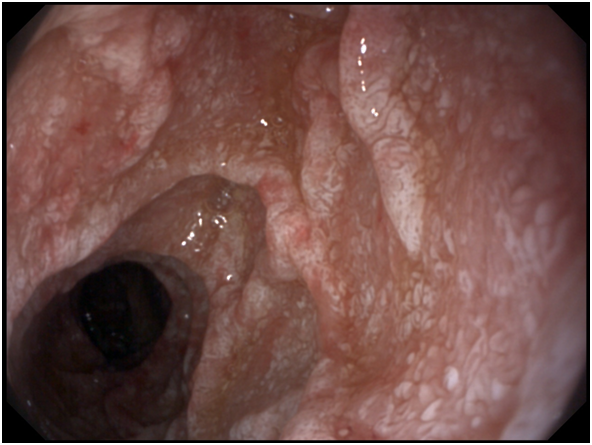

A 53- years old male presenting with chronic diarrhea of 8months duration, his diarrhea was of large volume, frothy in nature with foul odour. It was not related to a specific type of food, persisted during fasting with no diurnal variations. His condition was also associated with significant weight loss. The condition was associated with low grade fever and arthralgia of his both knee and hip joints. After 2months from the onset of his diarrhea he started to develop dizziness and easy fatigability. Physical examination of the patient was unremarkable apart from the pallor. Work up for diagnosing the cause of his diarrhea was done in the form of repeated stool analysis and culture, complete blood count, liver profile, renal profile, electrolytes, ESR, B2 microglobulins, virology (HIV, HBsAg, antiHCVab) and thyroid profile. All the previously mentioned investigations were normal apart from microcytic hypochromic anemia due to iron deficiency with haemoglobin=7.3mg/dl, serum Fe was 10mg/dl and transferrin saturation was 5%, also he had mild hypoproteinemia with serum total protein of 6.2g/dl and mild hypoalbuminemia with serum albumin of 3g/dl. His ESR was 123 and C-reactive protein (CRP) was 49mg/dl as shown in Table 1. Abdominal ultrasound was completely normal. Attempts of giving empirical medications in the form of metronidazole and quinolones failed to control the condition of the patient. Endoscopic intervention was decided in the form of upper endoscopy and colonoscopy. Total colonoscopy and terminal ileoscopy were done with no abnormality detected. For the upper endoscopy; the duodenal mucosa down to the proximal jejunum was markedly congested with extensive whitish mucosal patches as shown in Figure 1-3. Multiple biopsies were taken; histopathological examination showed focal villous distortion and focal villous erosions. The lamina propria showed mild mono-nuclear cell infiltrate with extensive infiltrate of foamy macrophages with dilated lymphatic spaces as shown in Figure 4. PAS (periodic acid shiff) stain was applied during microscopic examination where the organism was detected as shown in Figure 5. And hence the patient was diagnosed as a case of Whipple’s disease (WD). Then treatment was started accordingly in the form of ceftriaxone for 15days followed by trimethoprim-sulfamethoxazole (TMP/SMX) twice a day for 1 to 2years with marked improvement of the patient's condition. The improvement was evident by his laboratory parameters (Table 1) and endoscopic picture (Figure 6).

Figure 2 Whitish patches of Whipple's disease.

Diagnosis is made from duodenal biopsy, taken by upper endoscopy, which reveals pale yellow shaggy mucosa with erythematous eroded patches in patients with classic intestinal Whipple's disease25 and this is seen in our patient. Histopathological examination of the duodenal biopsies shows infiltration of the lamina propria with PAS-positive macrophages with intracellular clumps of T. whipplei.3 Immunohistochemical staining for antibodies against T. whipplei has been used to detect the organism in a variety of tissues, and a PCR-based assay is also available.26 Electron microscopy can be diagnostic showing coccobacillary bodies that represent the T. whippeli organism. Histologic examination with routine H&E and PAS stains is usually sufficient to reach a diagnosis, however, it is recommended that PAS-positive histologic findings to be confirmed with other methods when establishing the diagnosis of WD.25,26